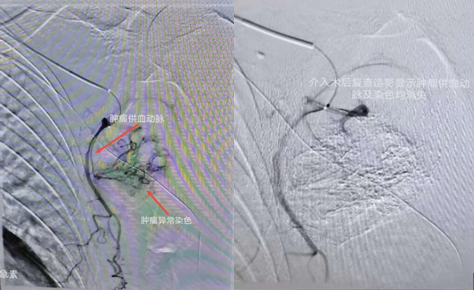

介入術(shù)中圖片

近日,吉林國文醫(yī)院淋巴瘤科與介入一科相互合作,成功為一例皮膚惡性黑色素瘤患者,實施了實體腫瘤動脈灌注化療栓塞術(shù),患者李某某10個月前曾確診為皮膚惡性黑色素瘤,腫瘤分布在左側(cè)腋下,患者既往曾多次行靜脈化療及免疫治療,但腫瘤病情仍然繼續(xù)進展,患者目前左側(cè)腋下腫瘤病灶增長較快,伴有局部脹痛感,淋巴瘤科左淑波主任綜合分析患者病情后,邀請介入一科韓長清主任進行共同商討治療方案,評估是否可行介入手術(shù)治療,經(jīng)兩位主任共同商討后決定,可給予患者行腫瘤供血動脈化療栓塞術(shù)介入治療。介入術(shù)中非常順利,成功尋找到腫瘤供血動脈并給予治療,術(shù)后患者恢復良好,疼痛癥狀有所改善。